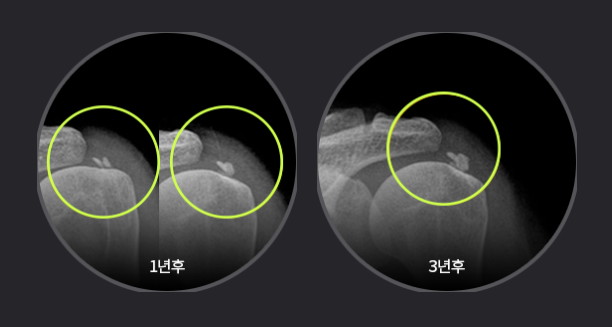

석회화건염.png

석회화건염의 치료는 힘줄의 염증에 따라 달라지는데요. 환자 석회 단계별 치료가 이뤄져야 하는 것이지요. 석회의 크기가 작고 통증이 적으면 스트레칭, 소염제 복용, 온찜질 정도로 회복이 가능하지만 이보다 심하다면 체외충격파, 약물치료, 물리치료, 주사치료 등 비수술 치료로, 이런 치료로도 통증이 줄어들지 않는다면 수술을 고려해야 합니다. 이때 수술을 한다고 끝이 아니라 체계적인 재활 시스템으로 어깨 운동을 회복시켜야 합니다.